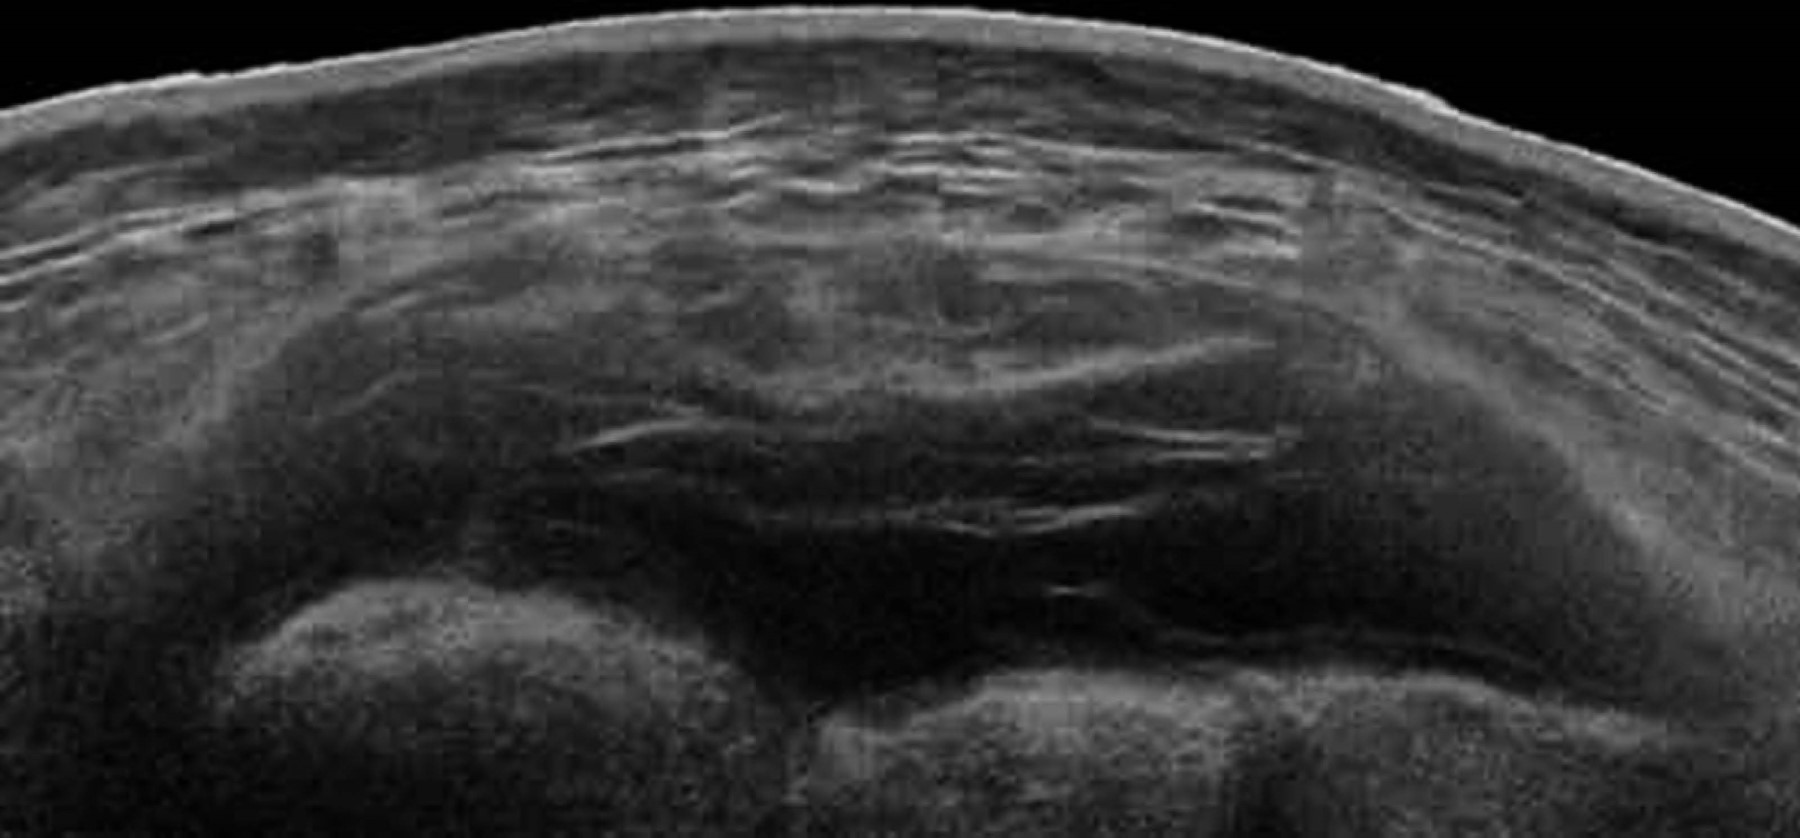

En radiografías simples de pelvis se identificó una fractura de la rama inferior de pubis izquierdo, el ultrasonido (USG) de tejidos blandos reveló una acumulación de líquido hipoecogénico entre el tejido celular subcutáneo y la fascia con dimensiones de 14 × 60 × 95 centímetros para un volumen de 426 ml, lo que indicaba una posible LML lumbar (Figura 1). La tomografía reveló una colección de líquido hipodenso, unilocular, entre la fascia y el tejido celular subcutáneo, con un volumen similar.

El diagnóstico de este tipo de lesiones se basa principalmente en el examen físico, algunos signos y síntomas pueden ser variables y elusivos, quemaduras por fricción y escoriaciones en la región lumbar pueden ser pistas para el diagnóstico. La hipermovilidad de la piel es otro signo clínico útil, en especial cuando el paciente presenta varios días después del trauma. La pérdida de la sensibilidad cutánea sobre el área lesionada puede ser consecuencia de cizallamiento de los nervios cutáneos. Una vez establecido el diagnóstico clínico se puede respaldar mediante estudios de imagen, el USG ofrece una manera rápida y accesible de establecer el diagnóstico, como se describió en nuestro caso. El USG puede mostrar una colección de líquido entre la fascia y el tejido celular subcutáneo, por lo general hipoecogénico y unilocular si se realiza en la fase aguda, esto puede cambiar con la cronicidad de la lesión, la cual se puede volver multilocular. Por otro lado, la resonancia magnética (RM) es el estudio de elección. Típicamente esta lesión se presenta como una colección de fluido entre las capas antes descritas, con aspectos variables en la RM, principalmente dependiendo en el tiempo transcurrido entre el trauma inicial y la cantidad de sangre, grasa y tejido linfático que se encuentre en él. Posteriormente, la presencia en T1 y T2 de un anillo concéntrico hipointenso que realza al gadolinio, sugiere fuertemente la presencia de una pseudocápsula que puede evitar la reabsorción del contenido. Mellado y colaboradores describen seis tipos de LML basadas en la forma de la lesión, presencia o ausencia de cápsula y características en la RM, así como signos de mejoría (Tabla 1).10 Los radiólogos deben conocer estos hallazgos de la RM para ayudar a los clínicos en el diagnóstico y elegir la mejor opción terapéutica. Además, el realce ocasional del gadolinio ha llevado a los radiólogos a confundirlo con un sarcoma de tejidos blandos como en el caso reportado por Zairi y colegas.11 La localización característica y la historia de trauma pueden ayudar a distinguir una LML de una neoplasia.

Figura 1